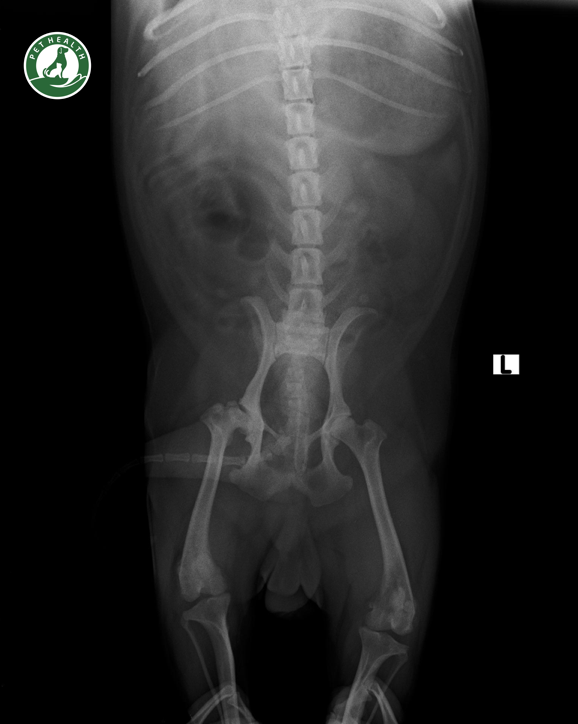

Các phương pháp chẩn đoán bệnh

Bệnh Loạn sản xương hông được chẩn đoán bằng sự kết hợp của hai phương pháp:Chụp X-quang khớp háng định vị đặc biệt và các phương pháp sờ nắn đặc biệt để xác định độ lỏng lẻo bất thường của khớp háng, cả hai đều cần thuốc an thần nhẹ.

- Phương pháp chụp x-quang chính xác nhất khi còn nhỏ là phương pháp phân PennHIP. Đây là một phương pháp định lượng đo lường các chỉ số của khớp háng thực tế. Nó dự đoán chính xác liệu một con chó con có phát triển chứng loạn sản xương hông hay không và những lựa chọn phẫu thuật nào sẽ phù hợp nhất để ngăn ngừa bệnh viêm khớp gây dẫn đến liệt chi sau.

- Theo dõi độ lão hoá của khớp hông: Tốc độ này có thể thay đổi ở từng con tùy thuộc vào mức độ lỏng lẻo của hông. Động vật nào bị bệnh nặng thì có thể thể hiện sự đau đớn ngay khi tuổi còn nhỏ. Như vậy nó cần các bài tập tích cực hơn. Nếu động vặt mắc chứng lỏng khớp hông nhưng không biểu hiện cho đến tuổi trung niên thì trong trường hợp này, tổn thương sụn tiến triển chậm hơn vì tình trạng lỏng lẻo khớp hông ít nghiêm trọng hơn. Bên cạnh đó, cần lập kế hoạch kiểm tra X-quang cho động vật mỗi 6 tháng để đo các chỉ số của khớp hông, đánh giá sự tiến triển.